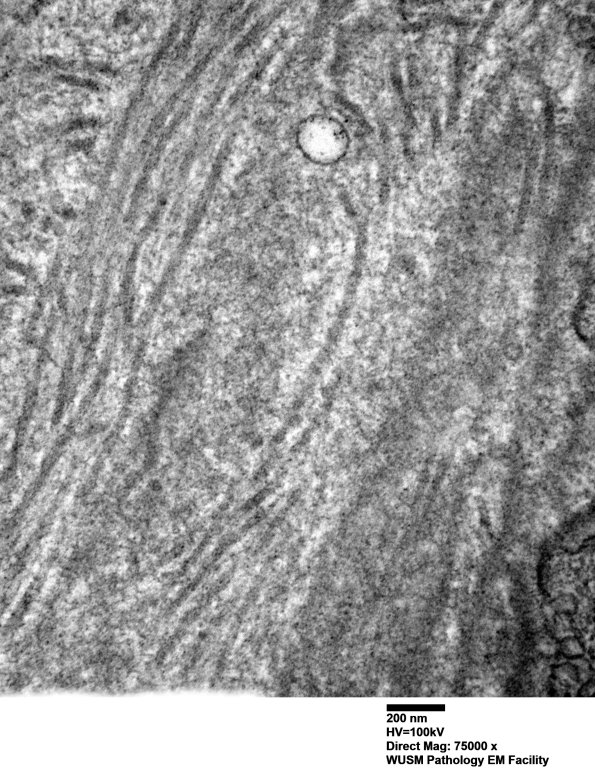

The endoneurial vessel shown here is expanded by collagen deposition with a small contribution by fragments of basal lamina. (electron micrographs)